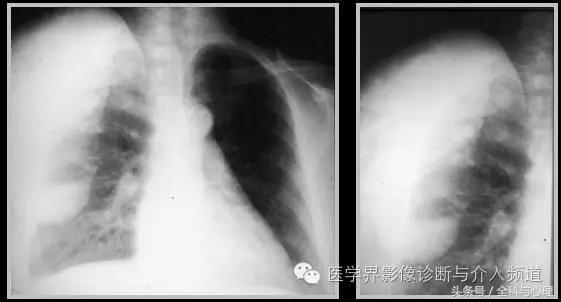

1、全身性钙质沉着症:皮肤、皮下或深部结缔组织钙化,与多种代谢紊乱及胶原血管病变有关,如皮肌炎,看起来像异位骨化,但没有真正的骨形成。开始为浅表的结节状或斑块状钙化,逐渐向更深的组织发展,表现为关节周围大片状钙化灶。

皮肌炎